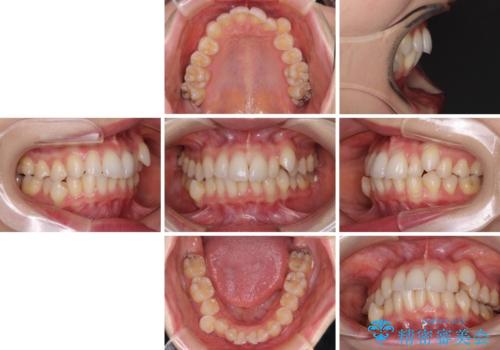

- 八重歯や前歯のデコボコを気にして来院された患者様です。

骨格的な左右差と、歯列から外れている歯が上下で左右非対称になっていることから、上下正中が歯1本分ずれている状態でした。

八重歯の改善と、上下の正中位置を極力合わせていくことを目的として、上下左右の第一小臼歯4本を抜歯し、ワイヤー装置にて矯正治療を行うこととしました。